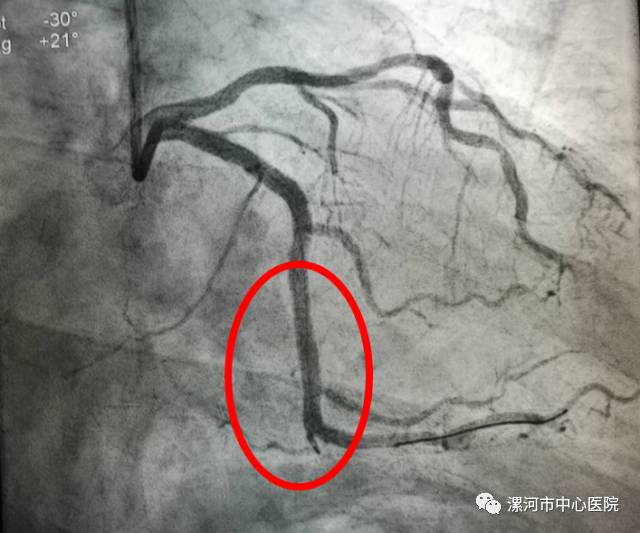

术后血管恢复通畅、光滑。